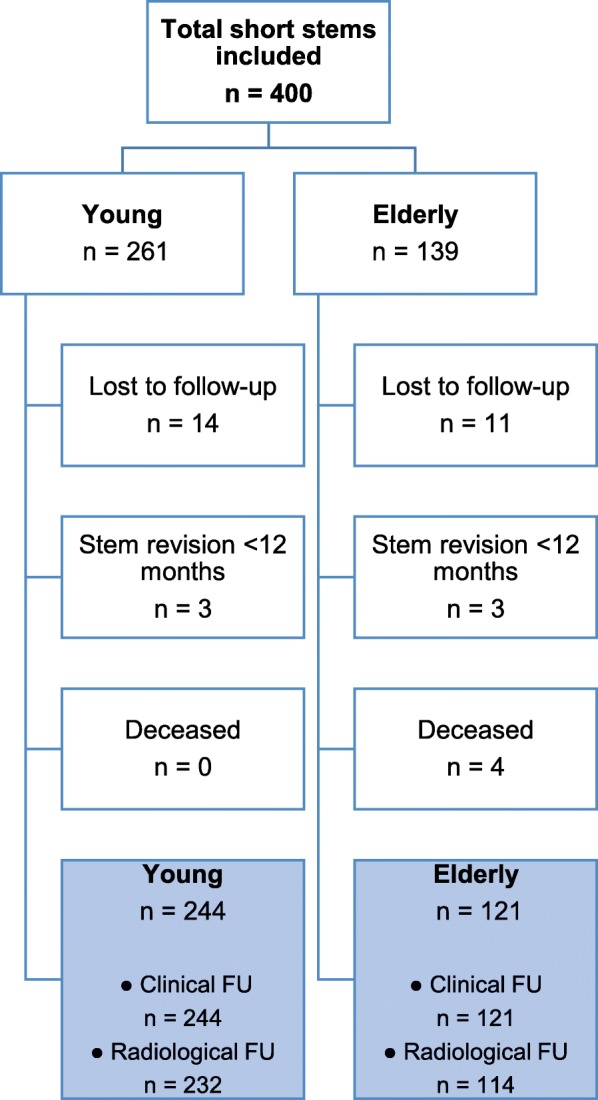

We identified 14 hips lost-to-follow-up in the young group and 11 in the elderly group. Four elderly patients were known to be deceased before the minimum follow-up of 12 months and 6 patients, 3 from each group, underwent stem revision for various reasons before the time point of 12 months of follow-up. Thus, for clinical follow-up, the young group (< 60 years) consisted of 244 hips in 214 patients with a mean age of 52.1 years (SD 6.7) and a mean follow-up of 52.0 months (SD 17.9; range 12.6–81.2 months) and the elderly group (> 75 years) consisted of 121 hips in 114 patients with a mean age of 79.1 years (SD 3.6) and a mean follow-up of 43.3 months (SD 21.3; range 12.0–75.5 months) (Fig. 2).

Fig. 2.

Study Flowchart